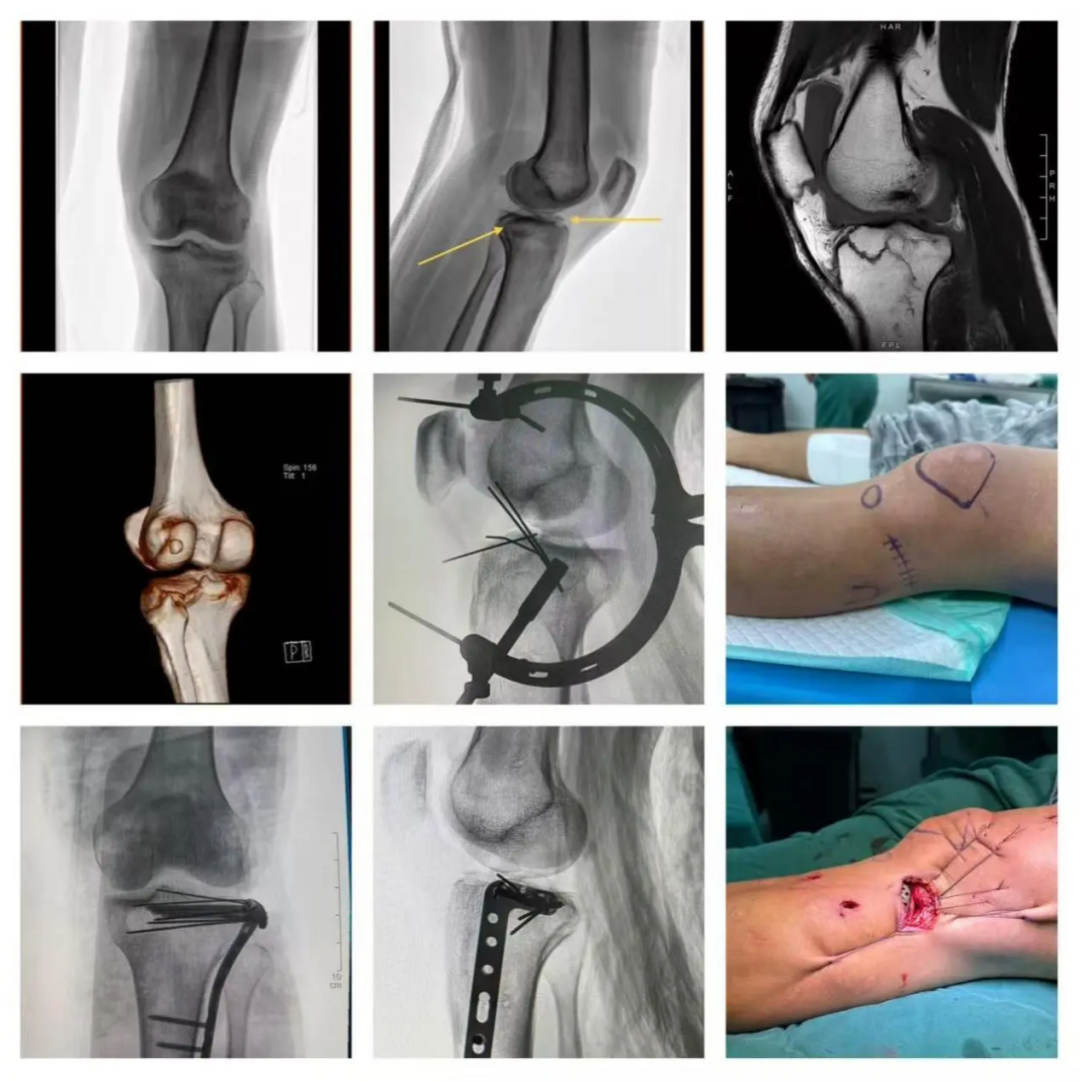

3. Case.03:76 岁,女性。右胫骨平台骨折(Schatzker V 型)